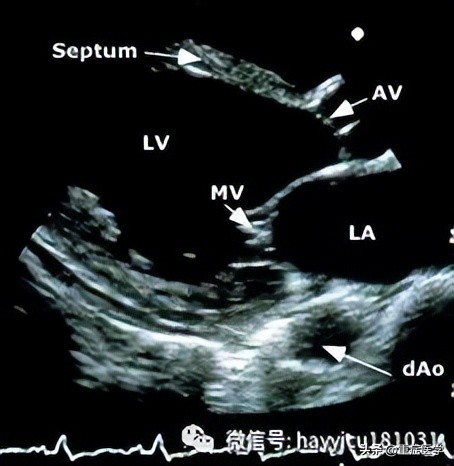

即时超声—POC超声的流程包括休克患者快速超声检查(rapid ultrasound in shock, RUSH)、重点心脏超声(focused cardiac ultrasound, FOCUS)以及休克患者腹部和心脏超声评估(abdominal and cardiac evaluation with sonography in shock, ACES),更常用作不明原因休克和低血压患者的便携式床旁诊断工具。当条件允许时,POC超声通常用于经临床和实验室评估未做出经验性诊断的患者,或进行确定性影像学检查不安全的患者(流程图 1A-B),也用作检查补液效果的辅助工具。虽然POC超声不能确定诊断,但我们认为,当由受过培训人员对有不明原因休克或低血压的危重患者将其作为时效性诊断工具使用时,可获得能挽救生命的有价值信息。多器官超声(RUSH、ACES)首先检查心脏,之后检查胸部、腹部和大血管;FOCUS仅检查心脏。不明原因的休克患者中POC超声采用的技术视图与在创伤患者中使用的(FAST)类似,将单独详细讨论。POC超声检查的组成将在下文简单介绍:首先,应该实施有限视图的心脏检查,查看下列部位:心包–心脏超声可能发现心包积液(无回声带);心腔塌陷,以及呼吸过程中右心室和左心室容积呈相反变化支持心包填塞为休克原因。心脏超声也可用于引导心包穿刺和检查引流效果。左心室–左心室偏大伴收缩力降低可能提示原发性泵衰竭,需要安排适当的干预(如心导管术)。相反,心腔较小和左室高动力可能提示脓毒症导致的分布性休克或血容量不足,分别需要进一步评估脓毒症来源或评估出血。左心室成像也可用于确定安置起搏器(经皮或经静脉)引起的心室收缩或室壁穿孔,或动脉瘤破裂。右心室–右心室收缩力降低可能提示右室心肌梗死;右心室扩大(如,右心室/左心室体积>1:1)可能提示大型肺栓塞或肺动脉高压;右心房/右心室中漂浮的血栓或移动的血凝块也支持肺栓塞。下腔静脉–呼气末下腔静脉(inferior vena cava, IVC)塌陷提示失血性或非失血性原因导致的血容量不足。下腔静脉扩张可能支持心包填塞或肺栓塞。第二,应对胸部和腹部进行简明成像来检查下列部位:肺和胸膜腔–无肺滑行征(视频 5)支持气胸的存在。肺水肿(证据为存在B线)可能支持原发性泵衰竭或继发于液体复苏的容量超负荷。胸膜腔积液(无回声带或分隔)支持脓胸或血胸,并可指导胸膜腔穿刺。腹膜腔–腹膜腔中有大量液体积聚的证据可提示创伤的出血源,或感染的潜在来源(即,肝硬化患者的自发性细菌性腹膜炎)。第三,应对大动脉和静脉进行简明成像以检查下列部位:主动脉–虽然首选胸部CT或经食管超声心动图,但POC超声可发现胸部或腹部动脉瘤或与主动脉夹层相符的内膜瓣。另外,查见游离液体、心包积液或胸膜腔积液也可作为动脉瘤破裂或动脉夹层的间接证据。近端下肢静脉–股静脉缺乏可压缩性可能提示深静脉血栓形成,从而提示临床医生怀疑肺栓塞。如果POC超声不具诊断意义或无法进行,只要条件允许应该进行确定性影像学检查,其中综合性超声心动图最有帮助。同样,如果从休克中成功复苏,采用标准影像学进行后续检查以证实通过快速床旁超声获得的诊断也是明智的。在不明原因的休克患者中,POC超声的优缺点包括: